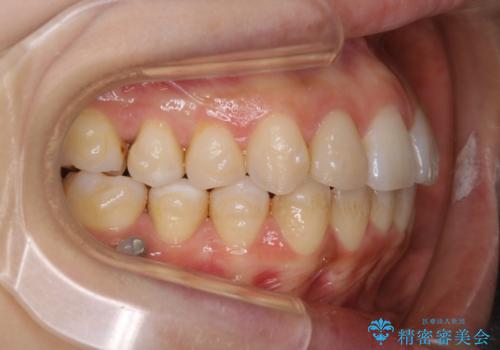

インビザラインの矯正中の方でアタッチメントが歯に付いているため、2ヶ月で着色やプラークが付いてきてしまいました。ホームケアや飲食の仕方により個人差はありますが、基本的には汚れが普段よりもつきやすいです。

定期的にクリーニングすることをおすすめします。